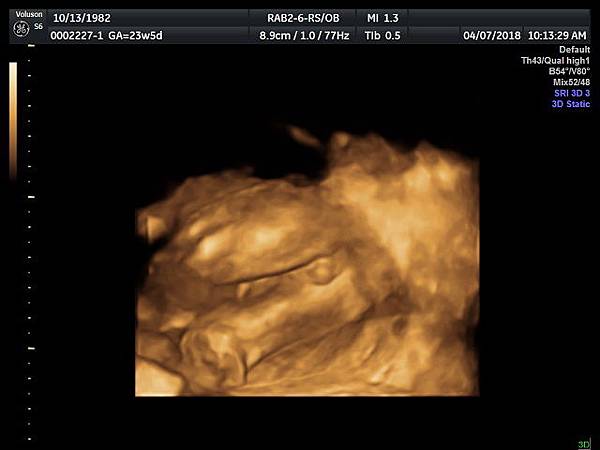

診斷尿道下裂常用的鬱金香sign(tulip sign)(附圖 10.11.),它的特徵就是龜頭陷入陰囊中間,胎兒如果是男生,一定要看到龜頭離開陰囊,這樣就沒有問題,每次遇到尿道下裂的個案時,我都會有一個感觸,男生如果能站著尿尿都要很感恩。